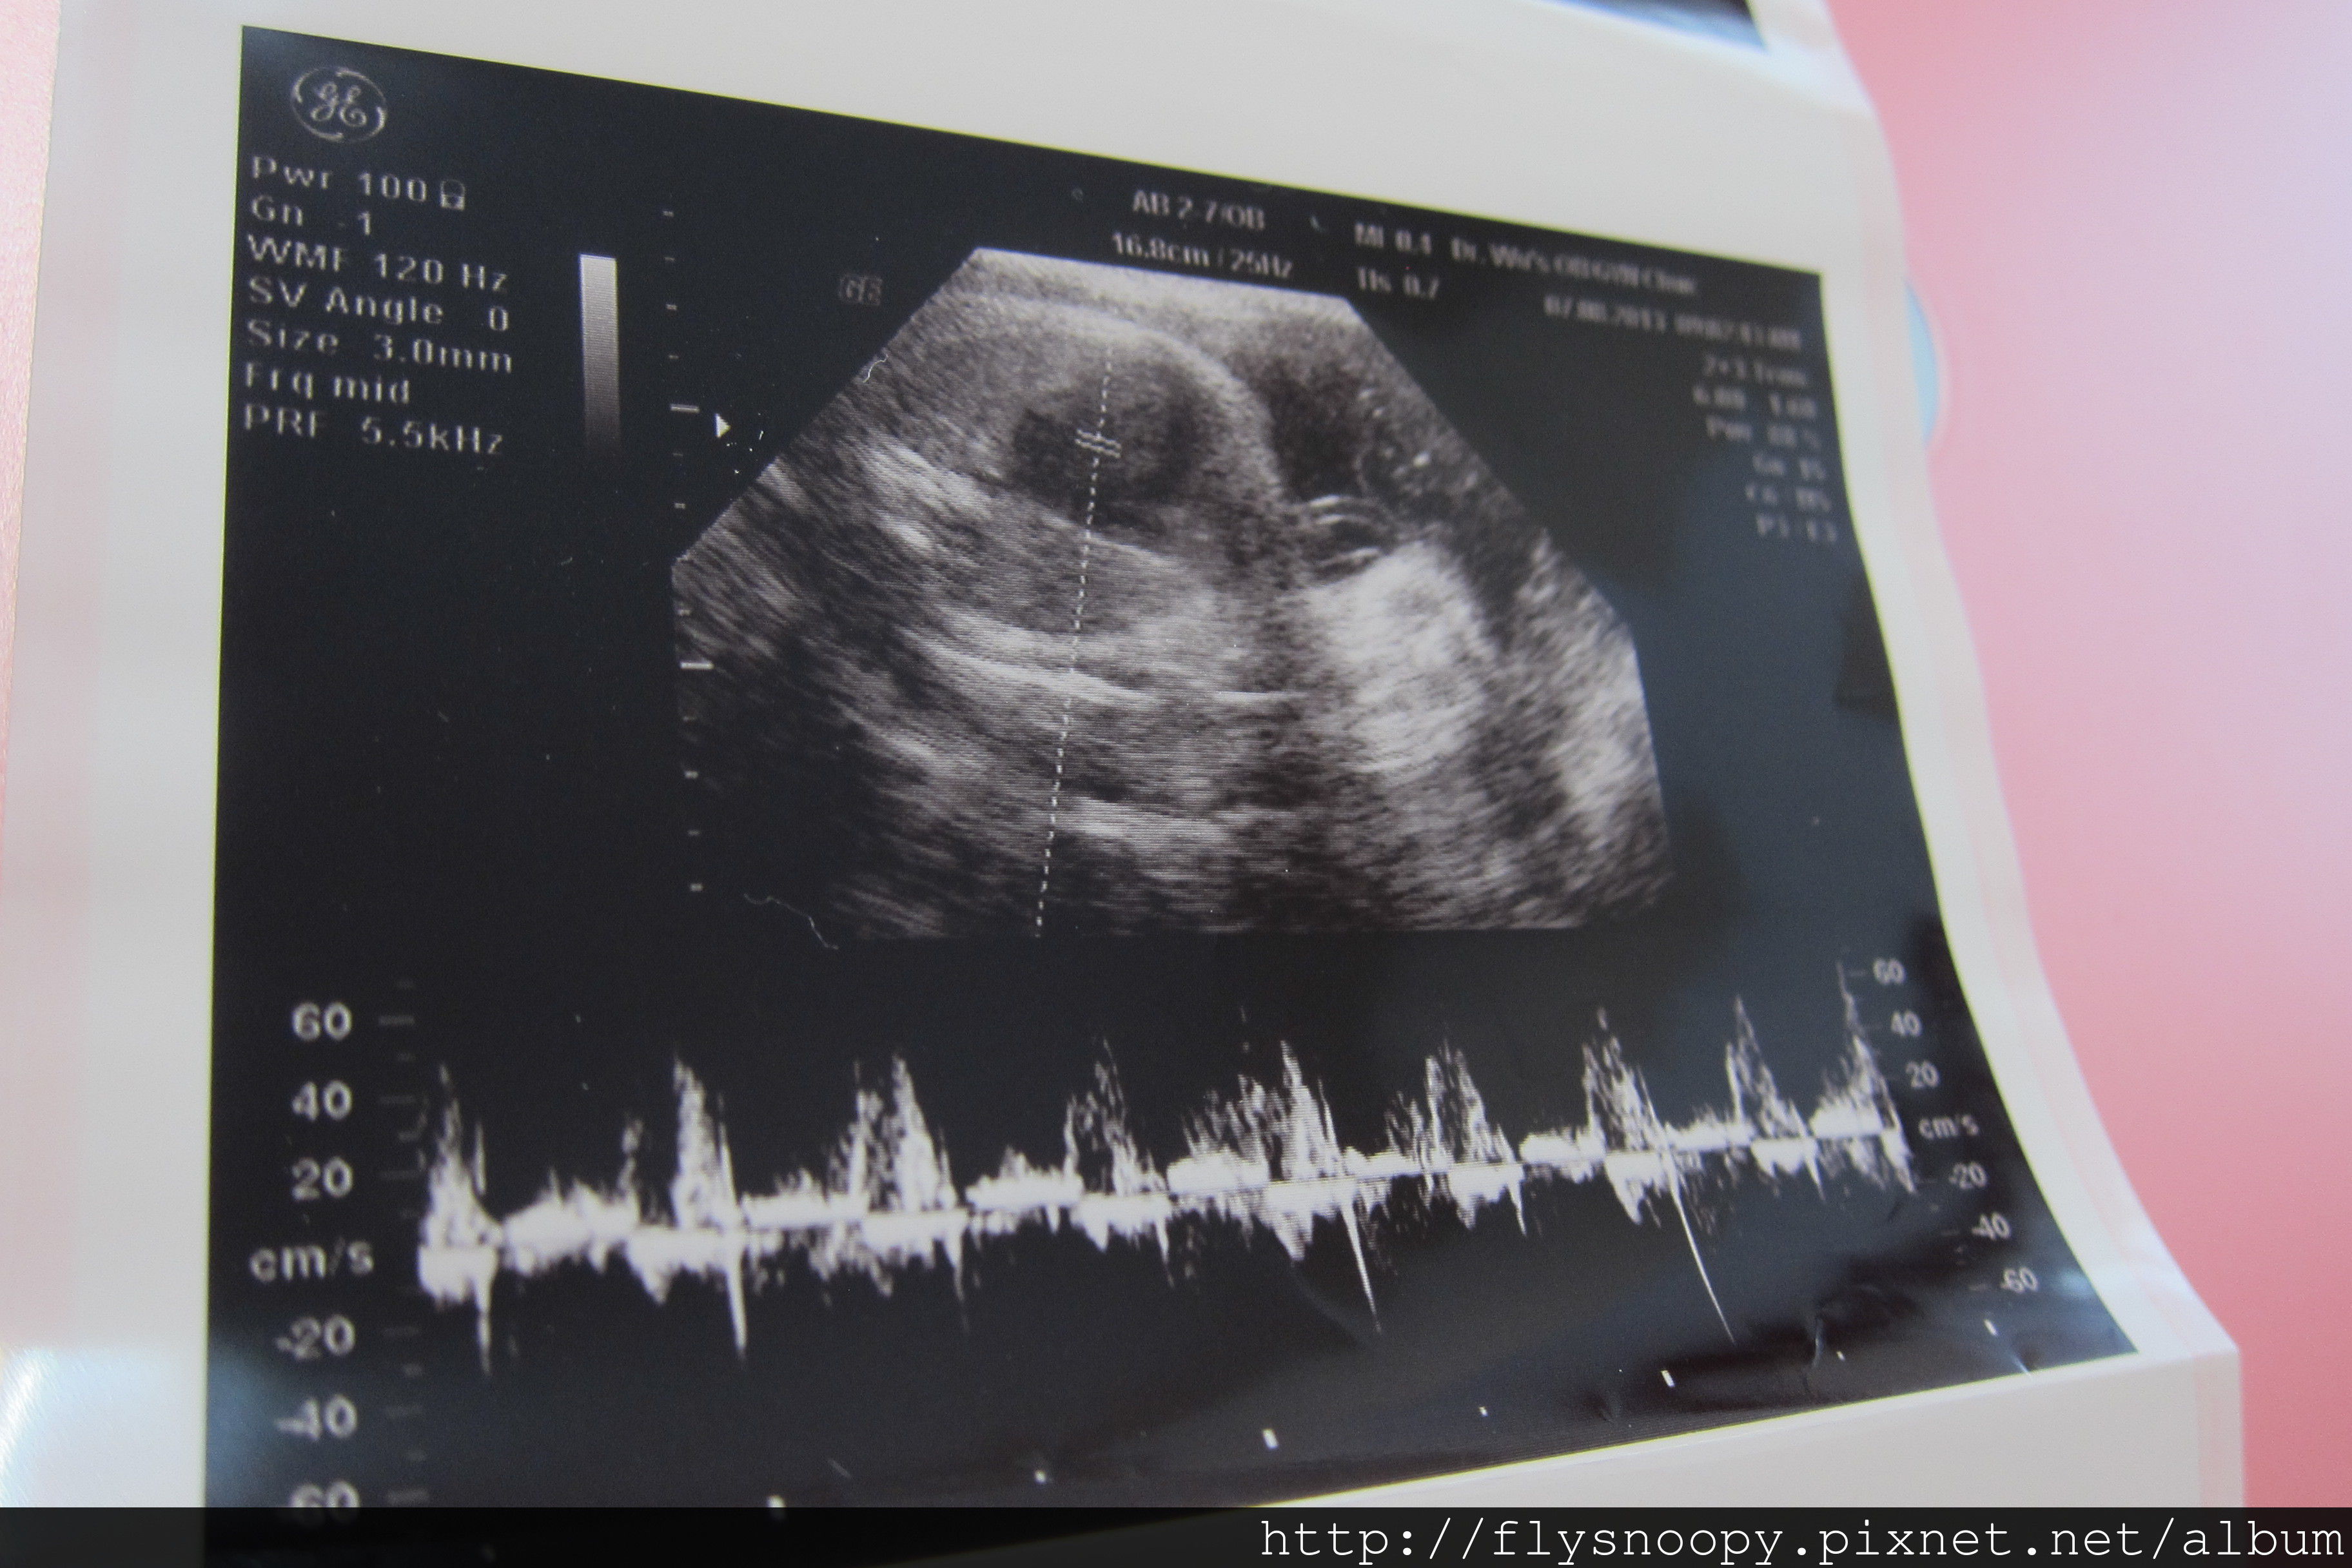

8/7第9次產檢

第九次產檢記錄

體重:64.7

血壓:119/72

尿糖、尿蛋白:正常

EFW:2399